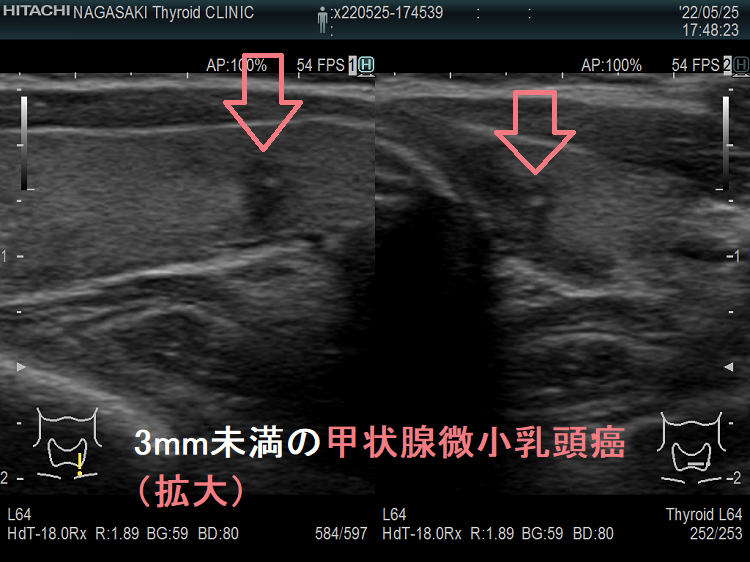

ケース⑤ 3mm未満の甲状腺微小乳頭癌

3mm未満の微小乳頭癌 超音波(エコー)画像

3mm未満の甲状腺微小乳頭癌 超音波(エコー)画像:通常倍率では、破壊性の変化か甲状腺腫瘍か判別できません。しかし、以下のように拡大すると

3mm未満の甲状腺微小乳頭癌(拡大) 超音波(エコー)画像

3mm未満の甲状腺微小乳頭癌 (拡大) 超音波(エコー)画像:拡大すれば微細石灰化を伴う辺縁不整・粗雑な甲状腺微小乳頭癌であるのがはっきりします。